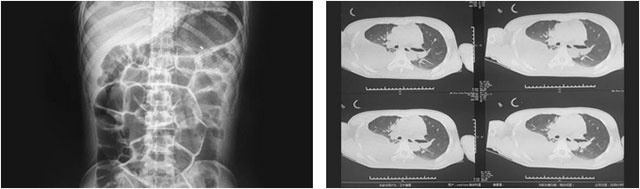

在该院经过半个多月的对症支持治疗后,小耿却仍然昏迷不醒。随着病情进一步恶化,小耿又被查出两肺挫伤,左侧气胸,两侧胸腔积液伴有肺膨胀不全,右侧胸腔积血,且伴有肠梗阻等病症,病情非常严重。随后,医院又对其进行胸腔闭式引流,予以禁食、胃肠减压等对症治疗,但仍无明显起色。

“脑干损伤、创伤性硬脑膜下积液、创伤性蛛网膜下出血、肺挫伤、肺部感染、创伤性气胸、创伤性血胸、创伤性胸腔积液、肠梗阻、低蛋白血症……”,潘仁龙主任介绍,患者刚来院时病情非常严重,其因外伤起病,多发损伤,其中最严重的是肠梗阻、右肺血气胸及肺部压缩严重,当时其胸腔血性积液非常严重,一天引流量约为170毫升,需及时治疗和控制。

▲ 来院时查体显示:多发损伤严重,肠梗阻、两肺挫伤及右肺血气胸